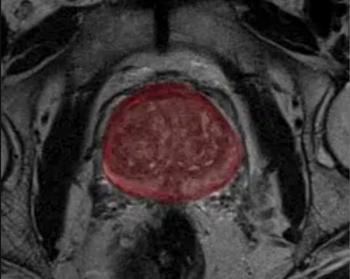

Emphasizing the proper diagnostic characterization of sidewall aneurysms, the authors of a new study found no significant differences in occlusion status or complications when they compared the approved use of intrasaccular flow disruption for bifurcation aneurysms to off-label treatment of sidewall aneurysms.